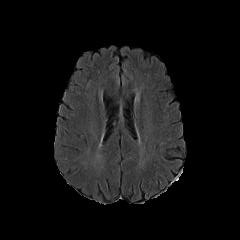

We observe that the generated normal-looking from ANT-GAN can also be used to directly segment the image, since the only difference between a synthesized normal-looking image and its real abnormal counterpart is region with the lesion. To illustrate this, we calculate the absolute difference between x𝑥x and 𝒢A2N(x)subscript𝒢A2N𝑥\mathcal{G}_{\rm{A2N}}(x) and show the segmentation after binary thresholding at 0.1 in Figure 9.

Refer to caption

(a) Tumor x𝑥x

(b) 𝒢A2N(x)subscript𝒢A2N𝑥\mathcal{G}_{\rm{A2N}}(x)

(c) Prediction

(d) Label

Figure 9: Example segmentation obtained by taking the absolute difference between the real tumor MRI x𝑥x and the generated normal-looking MRI 𝒢A2N(x)subscript𝒢A2N𝑥\mathcal{G}_{\rm{A2N}}(x), after binarization at a preset threshold.